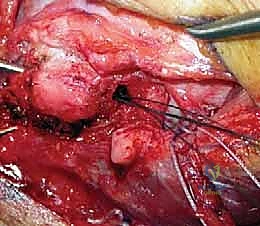

التدخل الجراحي: المعيار الذهبي

بالنسبة للغالبية العظمى من المرضى النشطين، والشباب، والرياضيين، تعتبر الجراحة هي الحل الجذري والوحيد لاستعادة استقرار الكوع ومنع التآكل الغضروفي المبكر (الخشونة). نظراً لأن الأربطة الممزقة بشكل مزمن تضمر وتفقد جودتها، فإن مجرد خياطتها (الإصلاح المباشر) غالباً ما يبوء بالفشل. لذلك، فإن الإجراء المفضل عالمياً والذي يبرع فيه الأستاذ الدكتور محمد هطيف هو إعادة بناء الرباط (Reconstruction) باستخدام رقعة وترية.